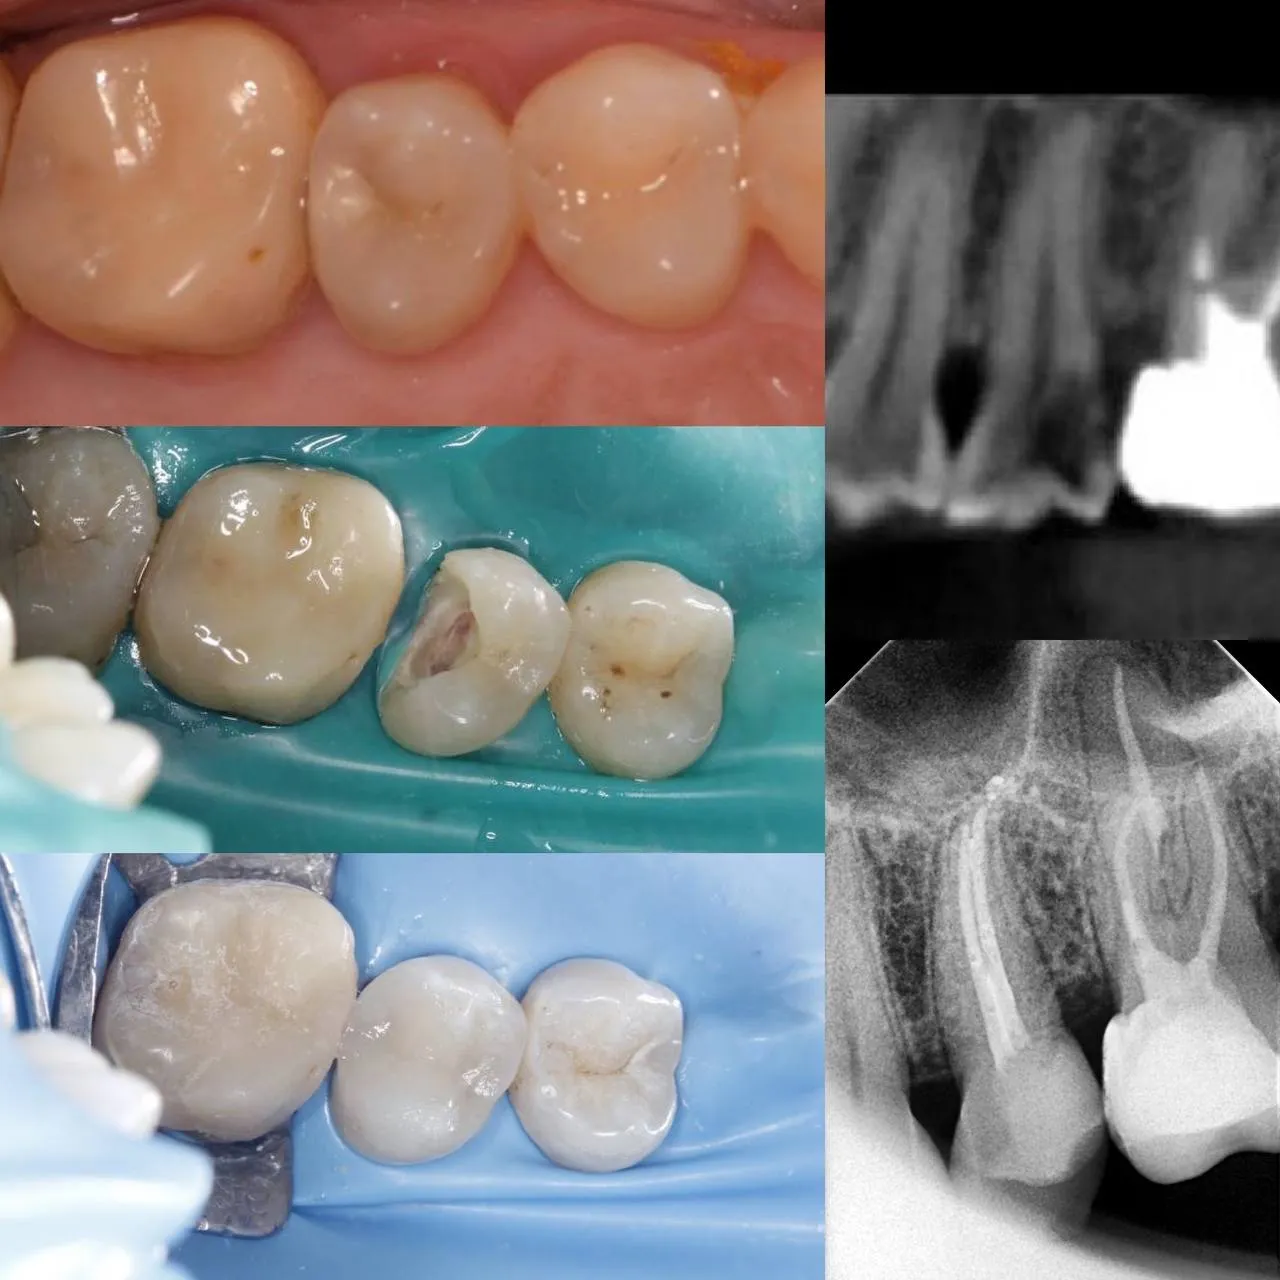

Вторинне ендо зуба 36 + підготовка

Лікування карієсу під мікроскопом зуба 16

Вторинне ендо 14 зуба. Пропущений дистальний щічний канал

Лікування незворотнього пульпіту зуба 15